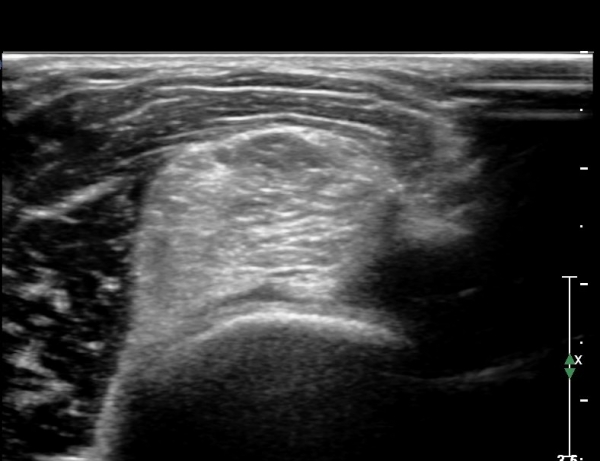

Å½ÃËÀÚ¸¦ Á¶±Ý ´õ ¸»´ÜÀ¸·Î À̵¿ÇÏ´Ï ¿ä°ñ ¸öÅëÀÌ °üÂûµÇ°í ÀÌÁú¼º°í¿¡ÄÚ Á¾±«¿Í Èİñ°£½Å°æ ºÎÁ¾ÀÌ °ýÂûµÊ(»çÁø 3).